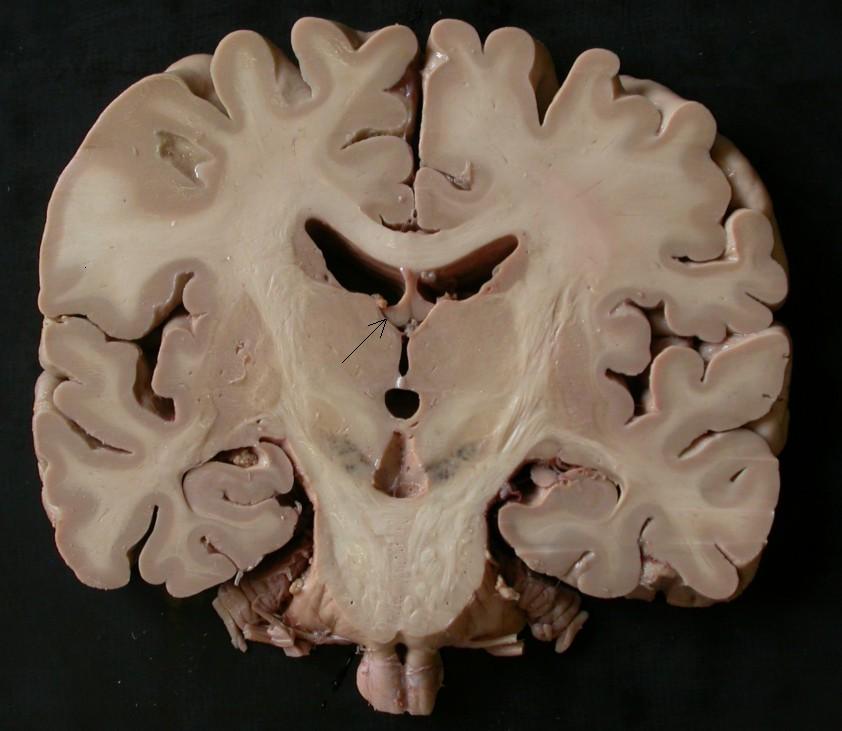

NEUROANATOMY I. - Structures of the CNS

Telencephalon; Cerebrum

Transverse cerebral fissure